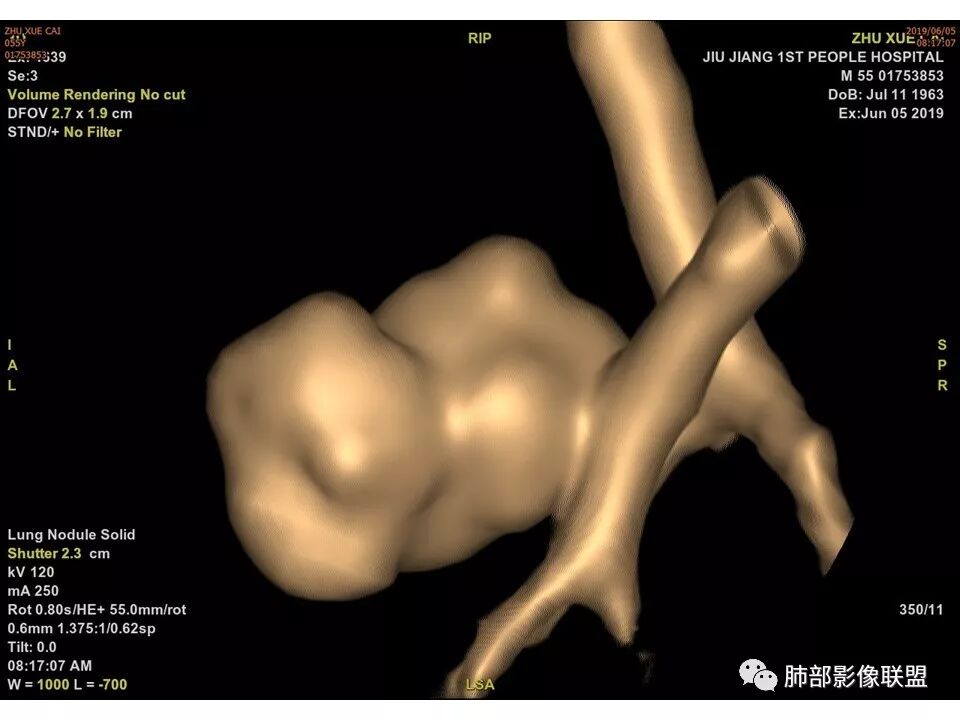

【每日晨读】肺良性小肿瘤竟然截断支气管,您见过吗?

病例资料

中年男性,左肺下叶不规则实性结节,有分叶及棘状凸起,支气管截断,轻度不均匀强化,考虑鳞癌,鉴别炎性肉芽肿。

左肺下叶前内基底段结节 深分叶和脐凹 表面部分膨隆 部分收缩 支气管截断 轻度强化 中央有坏死 考虑鳞癌 鉴别炎性结节

边缘有光滑,有圈黑晕,强化弱,似乎有脂肪密度,支气管截断的部位很自然,没有鼠尾状狭窄,考虑软骨型错构瘤?

病灶部分平直丶内收,有脂肪密度,不强化支持错构瘤。部分病灶有结节堆积感,分叶,与支气管、肺动脉关系密切,需鉴别腺癌。不强化进一步结核结节。

典型CT特征包括:(1)圆形或椭圆形边界清楚的病灶。(2)大小1~4cm,有轻微分叶改变。(3)较均匀的软组织影,多伴有钙化。(4)无毛刺,卫星灶及肺门或纵隔淋巴结肿大。(5)CT增强扫描无强化或轻度强化,其强化可能与软骨瘤间质中的薄壁血管或周围慢性炎症反应有关。